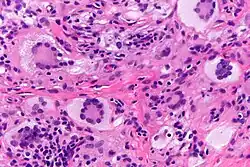

Touton giant cells are named for Karl Touton, a German botanist and dermatologist.[3] Karl Touton first observed these cells in 1885 and named them "xanthelasmatic giant cells", a name which has since fallen out of favor.[4] Karl Touton observed these giant cells when examining a biopsy or skin tissue sample from someone with a lesion under a microscope. He then classified and named these cells due to their strikingly unique appearance. Touton giant cells are still observed using these methods as well as staining with histological dyes such as hematoxylin and eosin (H&E).[5]

Touton giant cells, being multinucleated giant cells, can be distinguished by the presence of several nuclei in a distinct pattern. This pattern is described as a ring-like or wreath-like in the center of a cell. These cells contain a ring of nuclei surrounding a central homogeneous cytoplasm, while foamy cytoplasm surrounds the nuclei.[6][7] The cytoplasm is usually lipid-rich and has a foamy appearance. The cytoplasm is divided into two distic areas: the peripheral zone and the central zone. The central zone is the cytoplasm surrounded by the nuclei which is described as both amphophilic and eosinophilic. Meanwhile, the cytoplasm near the periphery of the cell, the peripheral zone, is pale and contains vacuoles due to the lipid content in this zone of the cell.[1][8]